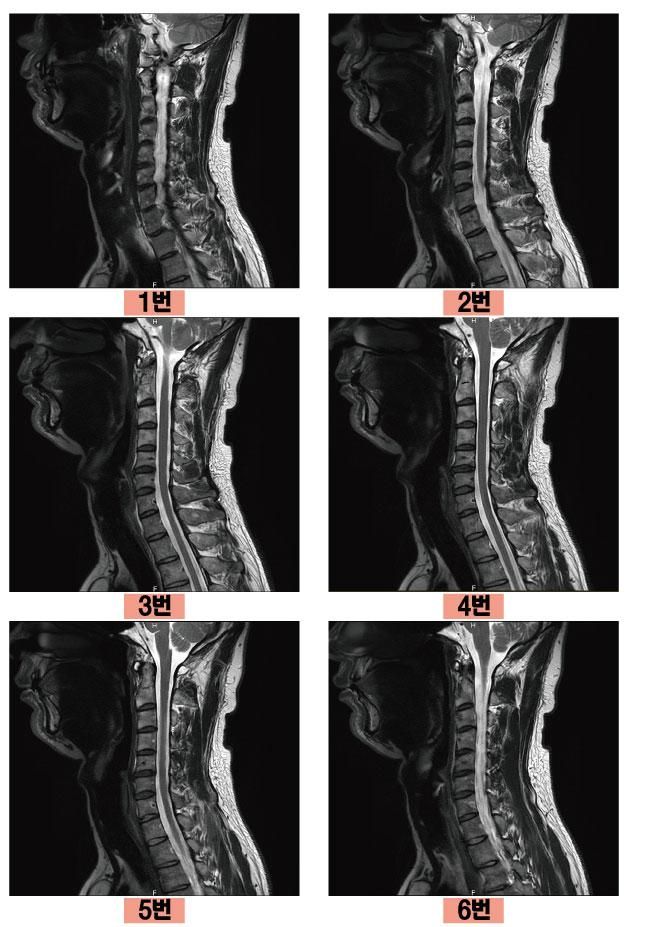

그래서 지난주에 경추,흉추 MRI를 촬영해봤는데 경추에서 5,6번에 퇴행성으로 보이는 증상이 좀 있었고 초기디스크? 경미한 정도라 신경을 누르는지도 애매한 상황이지만 누를수도 있고 아닐 수도 있는 그런 진단을 받았습니다. 척추센터도 3곳 정도 다녔는데 어떤 분은 근육의 불균형이 생기거나 압박이 생겨 신경을 누르는 것일수도 있다고 하며 체외충격파를 열심히 받아보라고 권유하시더라구요.

혹시 몰라서 경추 MRI 사진 첨부합니다.

• 1번 째 사진